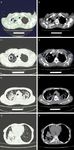

the main CT manifestation found in DM pa-

tients with PTB included large flakes of seg-

mental and lobar shadows, small patchy shad-

ows, wall-less cavities (Figure 3A, 3B), thick-

walled cavities (Figure 3C, 3D), thin-walled                   Mycobacterium TB [15, 16]. Another study

cavities, single cavities, multiple cavities (Fi-              exhibited that the continuous high level of

gure 3E, 3F), bronchial TB, bronchial inflation                blood glucose in DM patients significantly

signs (Figure 3G, 3H), proliferative nodules,                  reduces the immune activity of peripheral

enlarged lymph nodes and pleural effusion.                     blood lymphocytes [17]. The influence of PTB

There was a statistically significant difference               on DM includes the occurrence of PTB that

in the incidence rates of large flakes of seg-                 leads to glucose intolerance and this affects

mental and lobar shadows, bronchial inflation                  the glycemic control in DM patients. During

signs, wall-less cavities, multiple cavities, thick-           therapy, anti-tuberculosis drugs exert adverse

walled cavities and bronchial TB among the                     effects on blood glucose. Studies show that

classifications of good, general and poor glyce-               isoniazid, an anti-tuberculosis drug, can inhibit

mic control effects (P < 0.05), but there was no               liver cell enzymes, leading to the accumula-

statistically significant difference in the inci-              tion of active metabolites of glimepiride and

dence rates of single cavities, thin-walled cavi-              elevating the risk of hypoglycemia [18, 19].

multiple cavities of different sizes

in the upper lobe of both lungs

(E), and the mediastinal window

revealed multiple cavities of dif-

ferent sizes in the upper lobes

of both lungs (F). The pulmonary

window showed the consolidation

with bronchial inflation signs in

the right lower lobe (G), and the

mediastinal window revealed con-

solidation with bronchial inflation

signs in the right lower lobe (H).

Figure 3. CT imaging manifestations of DM patients complicated with PTB.     Mycobacterium TB and led to

The pulmonary window showed the wall-less cavity in the right upper lobe     the fusion and necrosis of

(A), and the mediastinal window revealed the wall-less cavity in the right

upper lobe (B). The pulmonary window suggested the thick-walled cavity       large lesions. In this case,

in the right upper lobe (C), and the mediastinal window showed the thick-    the number of CD8+ T cells

walled cavity in the right upper lobe (D). The pulmonary window indicated    increased remarkably, and the